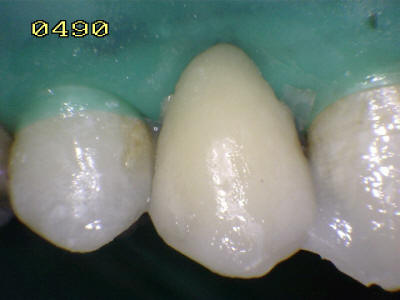

Aspecto vestibular del

r3emanente dentario

Eliminada la

caries, micro-arenado con óxido de aluminio y grabado total con

acido ortofosforico (Flechas blancas)